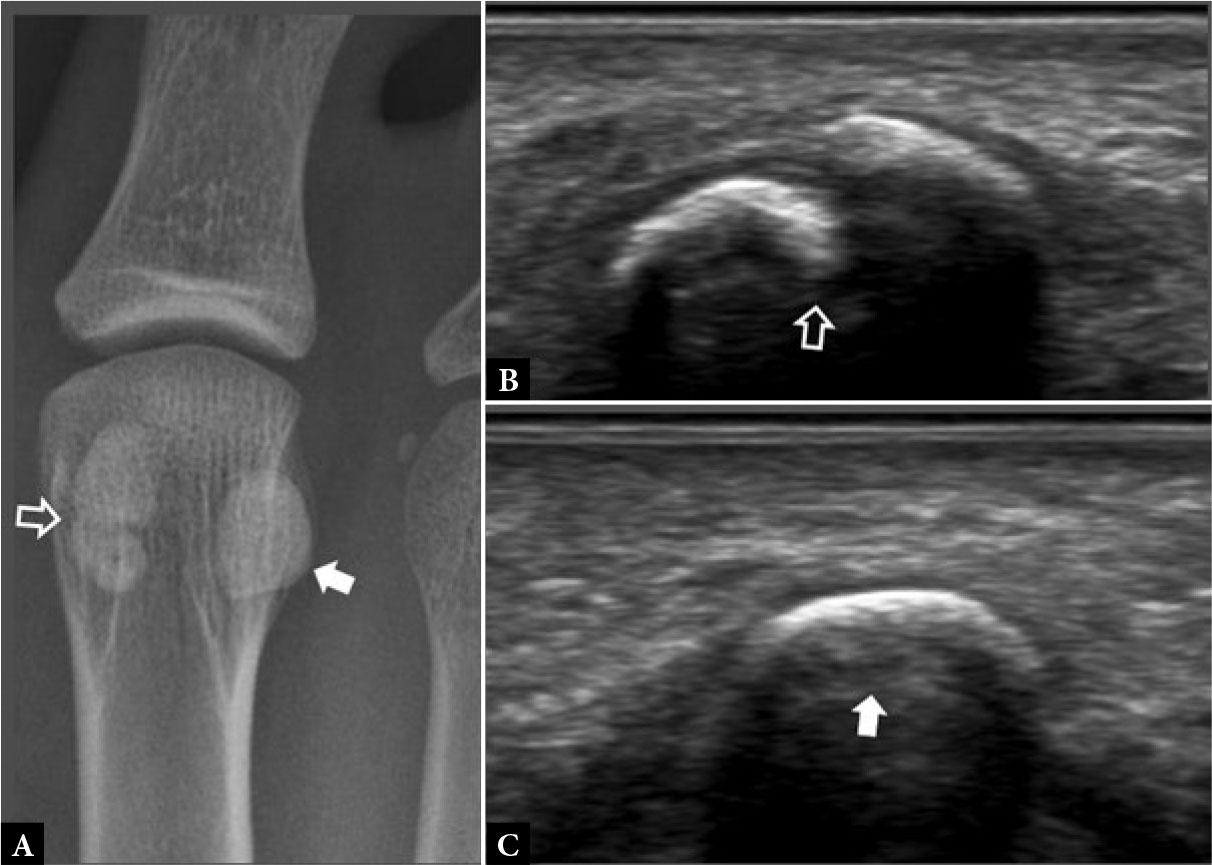

Fig. 1.

41-year-old female with forefoot pain and swelling for one month. There was no specific traumatic event and no undue sporting activity. A tendon injury was suspected clinically A. Dorsoplantar (DP) radiograph shows normal 2nd metatarsal bone (arrowhead). B. Longitudinal greyscale and C. color Doppler, and D. transverse greyscale US images show moderate severity localized periosteal thickening (open arrow) of the 2nd metatarsal shaft dorsally, with moderate adjacent soft tissue thickening (open arrowhead) consistent with active stress fracture. E. Radiograph three months later showed marked periosteal thickening of the 2nd metatarsal shaft (arrow) compatible with healed stress fracture